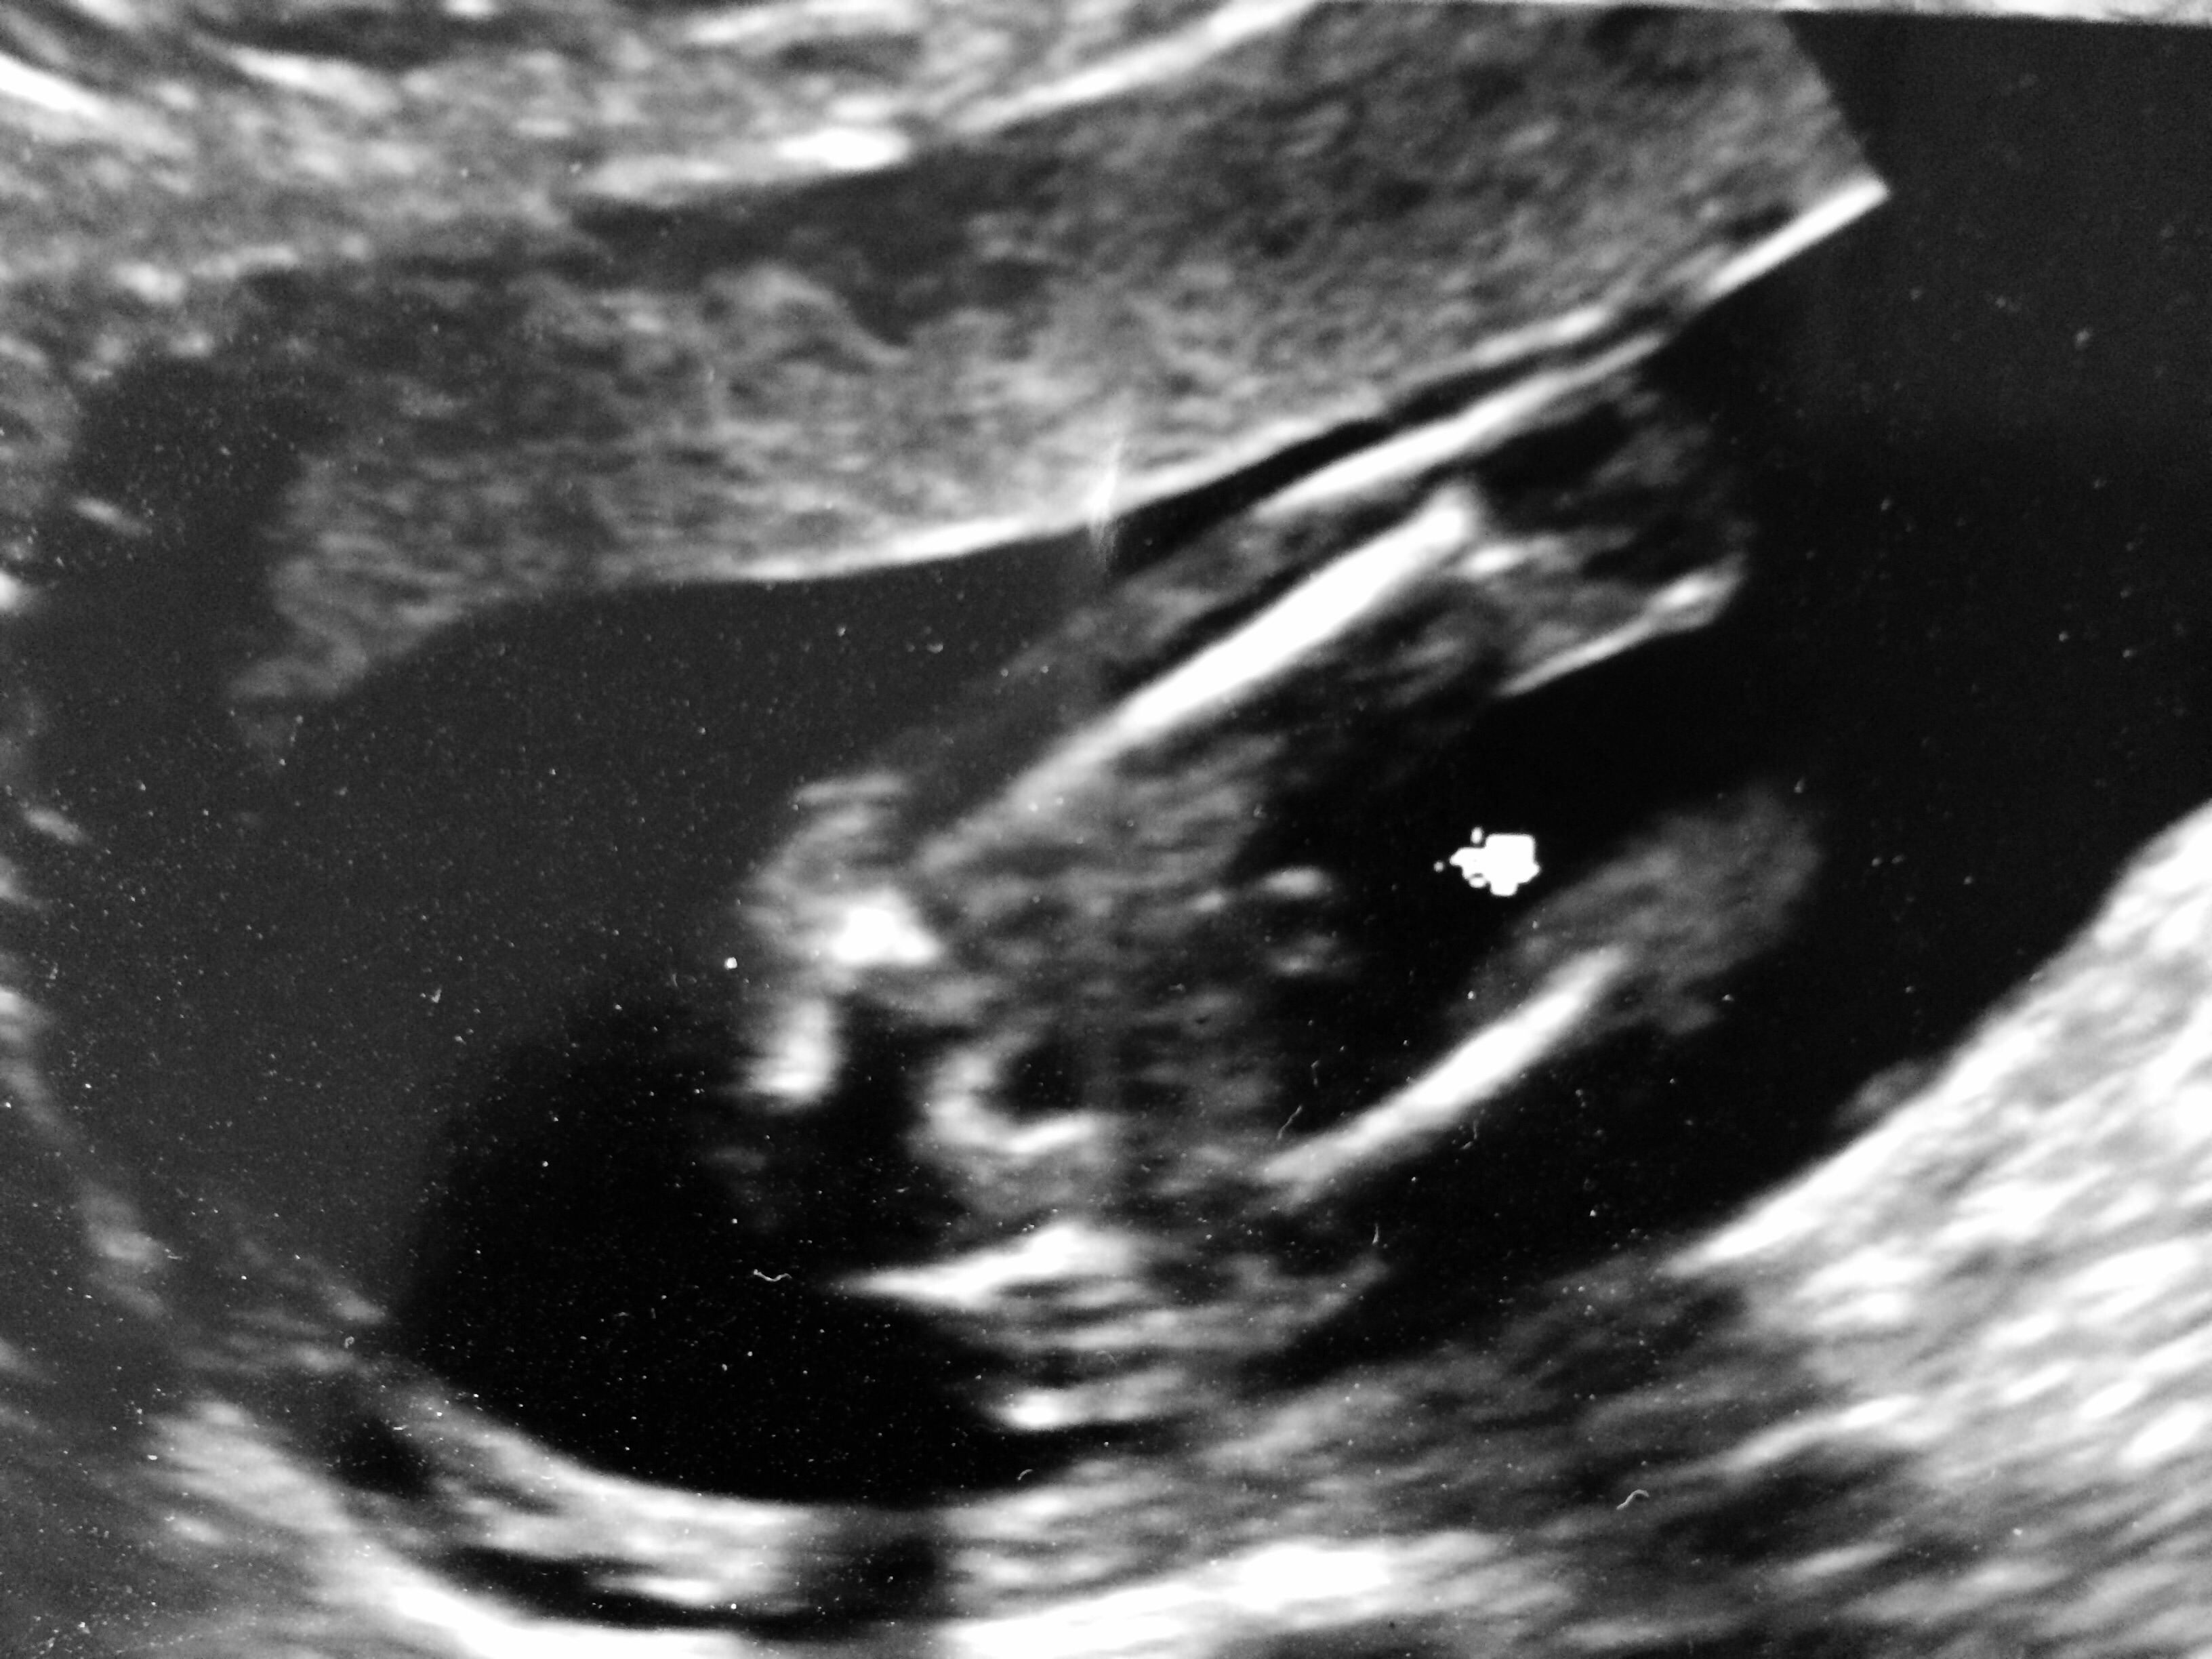

Had "gender sneak peek" at 16 weeks at private 3D place. Tech thinks boy but I'm not convinced. Any help is appreciated!! Attachment 24636

Looks like a boy

Yes that is a boy.